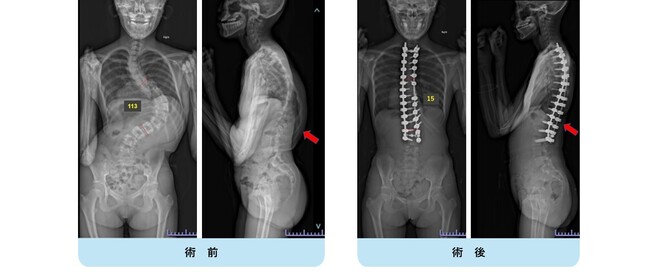

思春期特発性側弯症が高度に進行した症例です。最大側弯角度は113°であり、100°を超える側弯の手術は一般的に神経合併症が危惧されます。神経合併症を極力防ぐため、また侵襲を低減する目的で、同じ入院期間に2回に分けて段階的に矯正手術を行いました。1回目に最も側弯の強い箇所に対して側方から椎体間解離を行い、2回目に後方から全体のバランスが良くなるように慎重に矯正固定術を施行しています。

神経合併症はなく、術後の最大側弯角度は15°に改善(矯正率:87%)、背中の大きなコブも無くなっているのが分かります(赤矢印)。神経合併症が発生しないように慎重に手術を行うのは当然ですが、側弯を治すだけでなく横から見た姿勢を治すことにも留意しています。